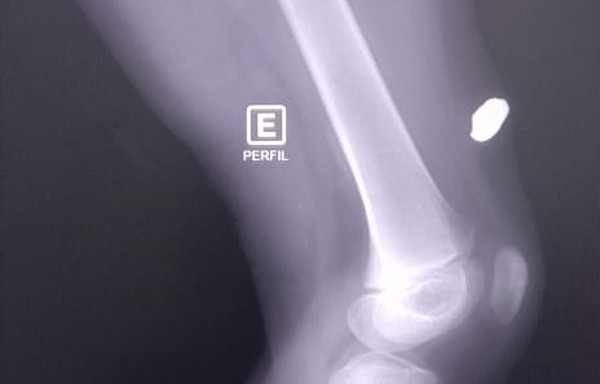

| Bala perdida atravessa parede e atinge perna de criança que dormia em casa no interior do Amazonas. — Foto: Rede Amazônica |

Uma bala perdida atravessou a parede e atingiu a perna de uma criança que dormia na casa onde mora no município de Itacoatiara, no interior do Amazonas, na manhã deste domingo (19). Familiares contaram que a bala ficou alojada e viram uma viatura da Polícia Militar deixar o local após ouvirem o barulho do tiro.

Ainda segundo a mulher, a criança deve passar por uma cirurgia para retirar a bala que ficou alojada na perna dela. Vizinhos contaram para a mãe da vítima que os policiais teriam abordado um homem na rua onde moram, quando o disparo foi feito.